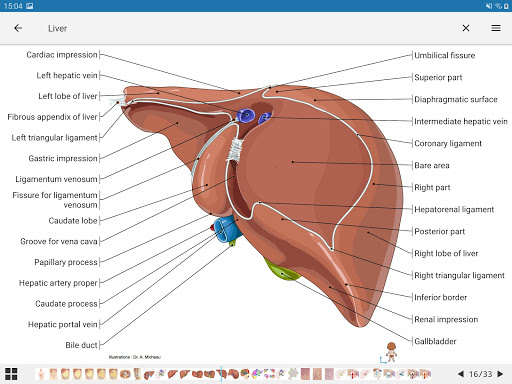

e-Anatomy tiene más de 26 000 imágenes que contienen series de imágenes en vistas axiales, coronales y sagitales, así como radiografías, angiografías, imágenes de disección, gráficos anatómicos e ilustraciones. Todas las imágenes médicas fueron etiquetadas cuidadosamente, más de 967 000 etiquetas disponibles en 12 idiomas, incluida la Terminologia Anatomica latina.

- Toque las etiquetas para mostrar las estructuras anatómicas